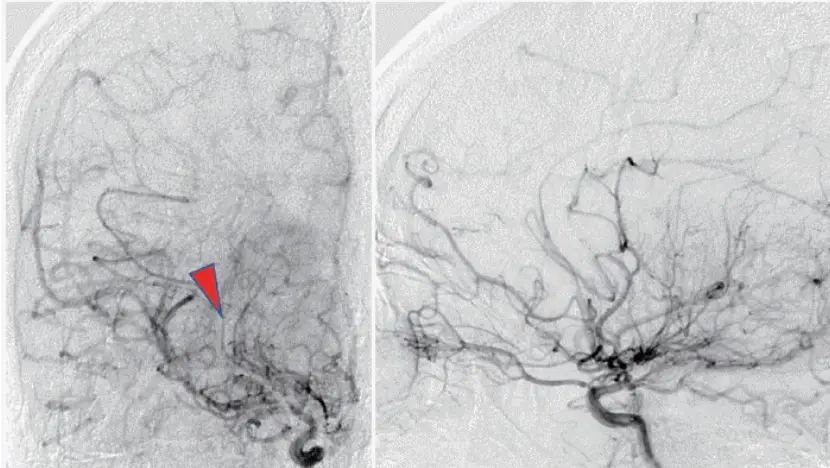

모야모야병(Moyamoya Disease, MMD)은 뇌 주요 혈관, 특히 내경동맥과 그 분지에서 점진적인 협착과 폐색이 발생하는 희귀 뇌혈관 질환입니다. 이 질환은 "연기와 같이 흩어지는" 모습의 비정상적인 측부 혈관 네트워크 형성을 특징으로 하며, 이 모습이 일본어로 '모야모야'(흐릿한 연기)처럼 보인다고 해서 이름이 붙여졌습니다.

모야모야병은 허혈성 뇌졸중, 일과성 허혈 발작(TIA), 두통, 발작, 인지 장애 등 다양한 신경학적 증상을 일으킬 수 있습니다. 이 질환은 동아시아 국가, 특히 한국과 일본에서 더 높은 유병률을 보이지만, 전 세계적으로 발생할 수 있습니다.